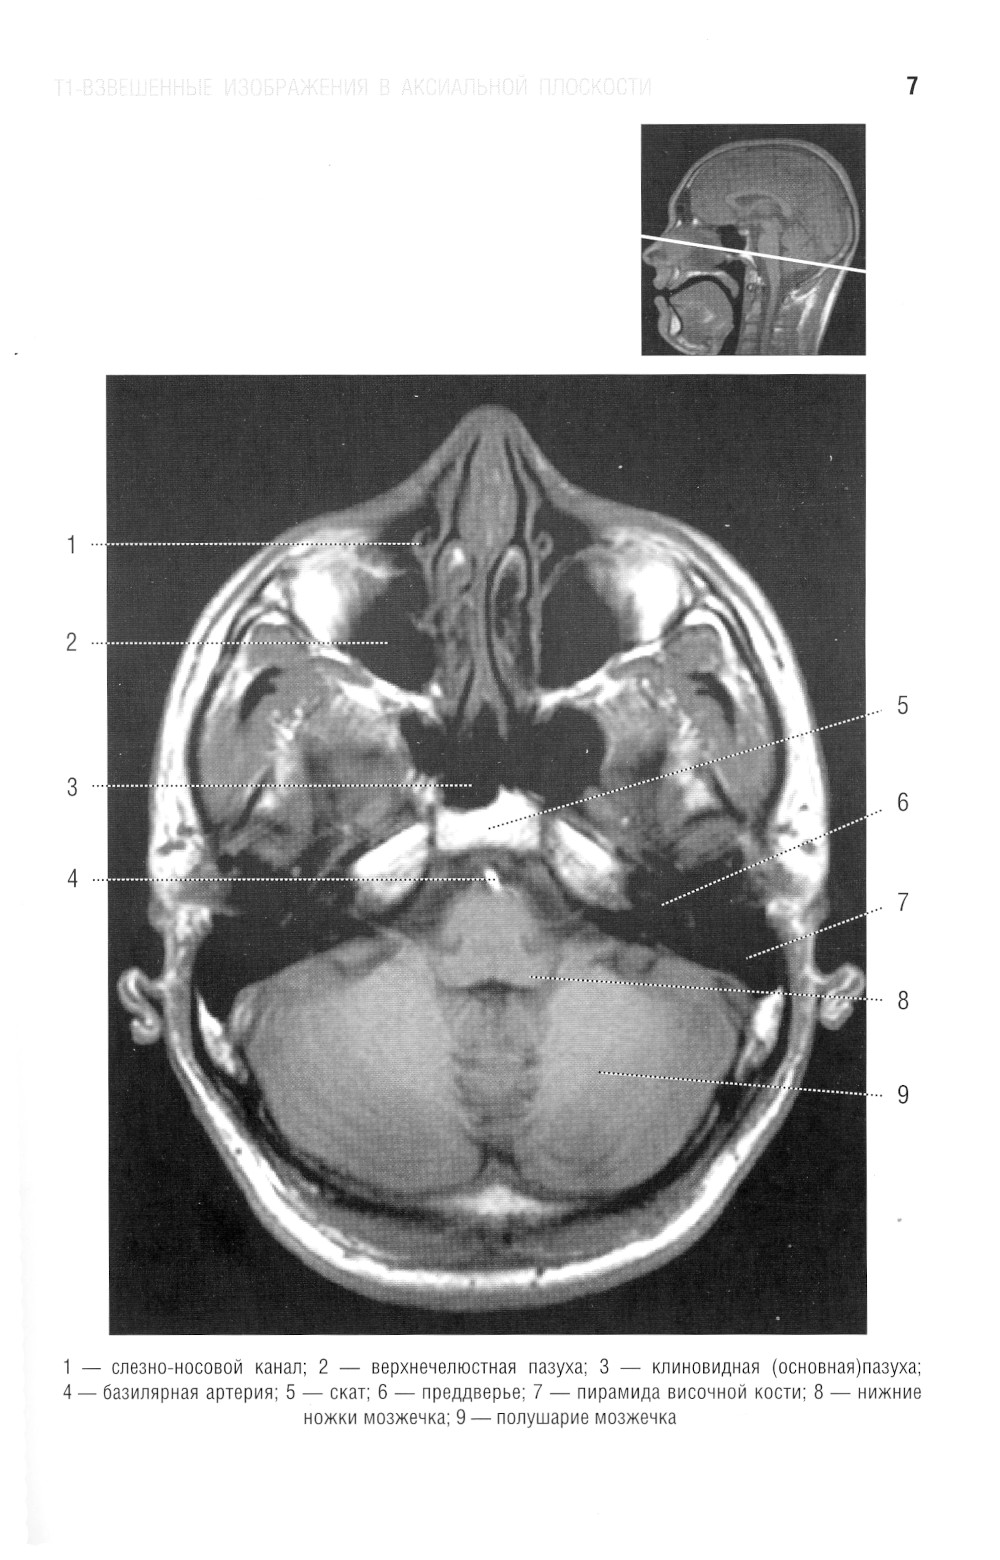

В руководстве представлена нормальная анатомия головного мозга и позвоночника по данным МРТ- и КТ-исследований. MPT-изображения головного мозга отражены в трех взаимно перпендикулярных плоскостях. Отдельная глава посвящена визуализации и нормальной анатомии сосудов головного мозга, в том числе с изображениями, получаемыми при бесконтрастной магнитно-резонансной ангиографии. Для врачей-рентгенологов, специалистов КТ и МРТ, невропатологов, нейрохирургов, а также врачей смежных специальностей. Руководство рекомендовано для обучения студентов медицинских вузов, а также может использоваться в системе последипломного профессионального образования.| Издательство | Элби |